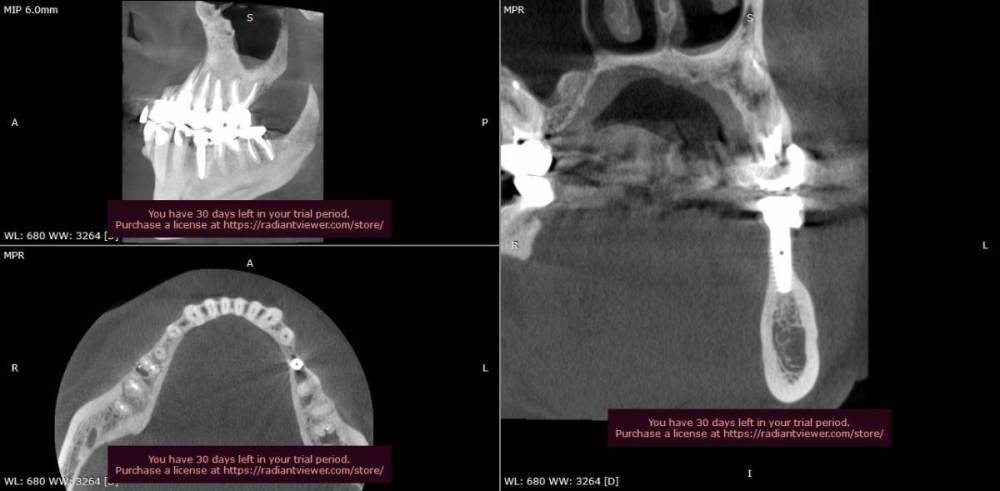

Ljocha Опубликовано 31 августа, 2022 Автор Поделиться Опубликовано 31 августа, 2022 приветствую! хотел бы спросить различные мнения: как считаете, такое иметь право на жизнь или надо выкручивать? установлен в апреле 2020, в приложении 2-х летняя динамика спасибо! Ссылка на комментарий

Ljocha Опубликовано 31 августа, 2022 Автор Поделиться Опубликовано 31 августа, 2022 все срезы выставлены синхронно вот так Ссылка на комментарий